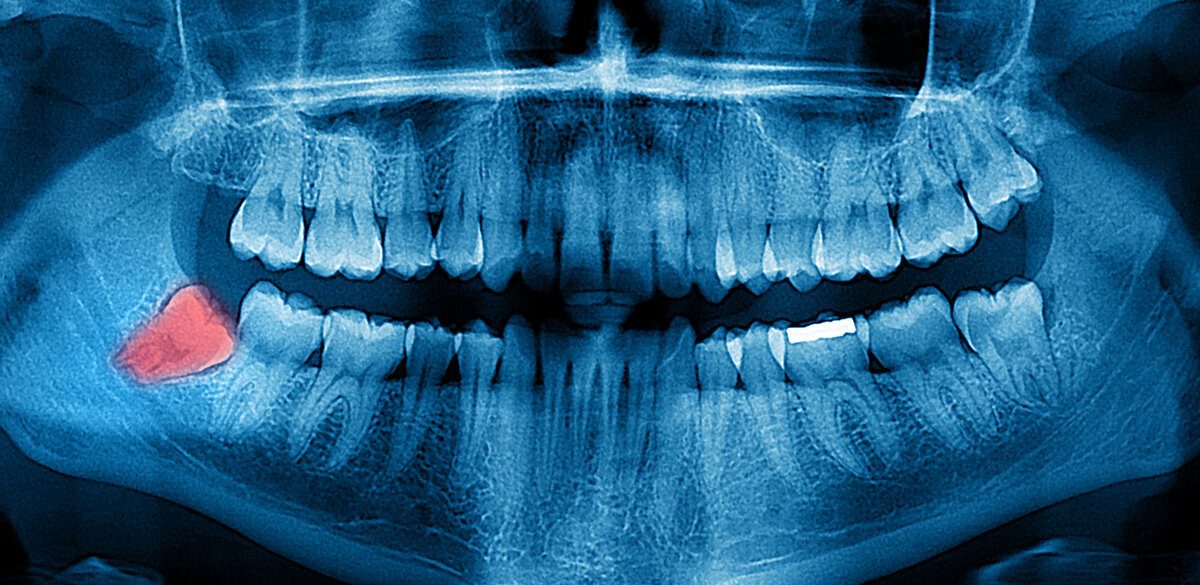

У взрослого человека максимальное количество зубов - 32 (в отдельных случаях их бывает и больше, это так называемые сверхкомплектные зубы - явление редкое). Четыре из них, самые крайние в верхнем и нижнем зубном ряду – это зубы мудрости. Учитывая их расположение в ротовой полости, имеют место определённые неудобства при проведении гигиенической чистки и лечебных мероприятий.

Зачем нужны зубы мудрости и почему они растут?

Со временем люди стали обрабатывать пищу перед употреблением: жарить, варить, парить, резать, молоть, перетирать. Она становилась более мягкой, в связи с чем со временем, в ходе эволюции, челюсть человека стала меньшего размера, и постепенно исчезла необходимость в четырёх крайних зубах. Несмотря на это, у многих людей имеются зубы мудрости.

На сегодняшний момент у 50% населения планеты зубы мудрости не прорезываются вообще.